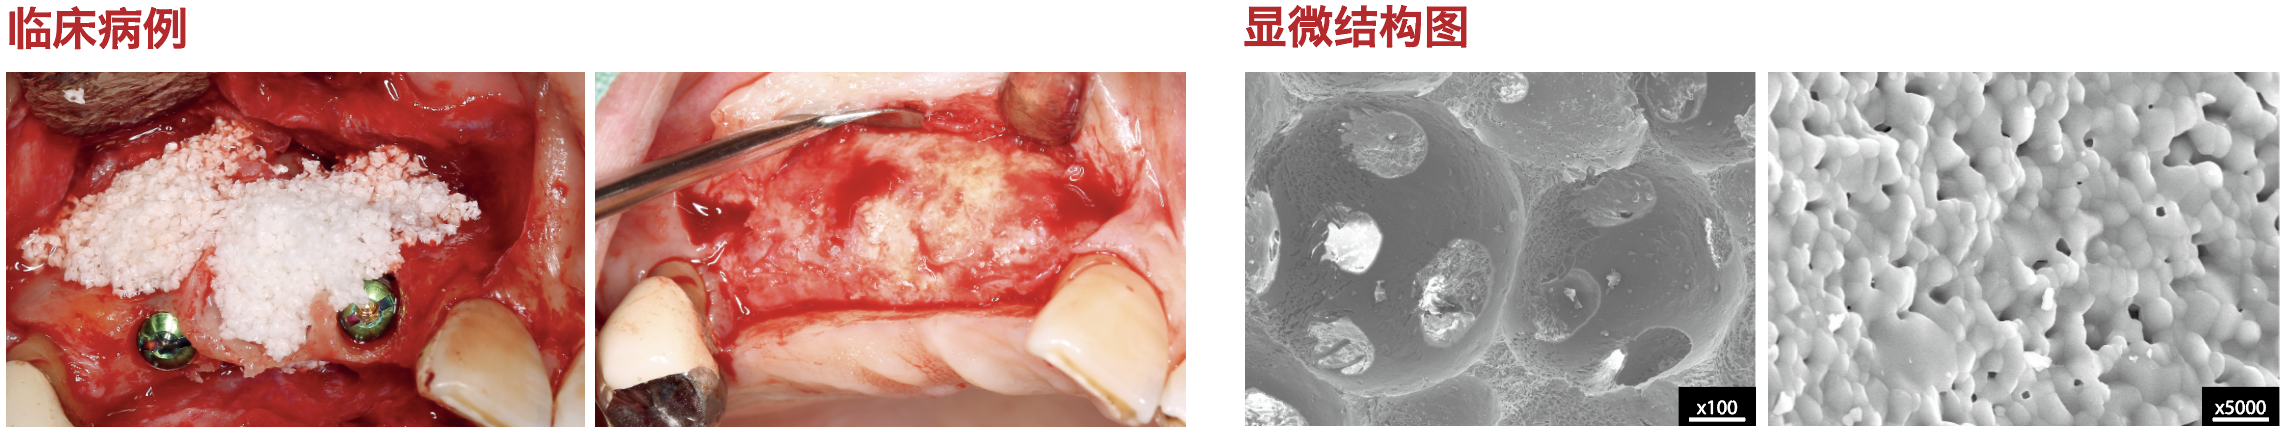

OSTEON? 3 牙科骨粉用于填充到因牙槽骨缺損而造成的不受咀嚼力的塌陷部位

例如: ? 牙槽嵴增量 ? 拔牙窩填充 ? 牙槽骨缺損

OSTEON? 3 牙科骨粉的特點

? 雙相磷酸鈣結構:60%HA(羥基磷灰石)+40%β-TCP(β磷酸三鈣)

? 全合成材料,良好的骨引導性

? 孔隙率:85% ± 10%